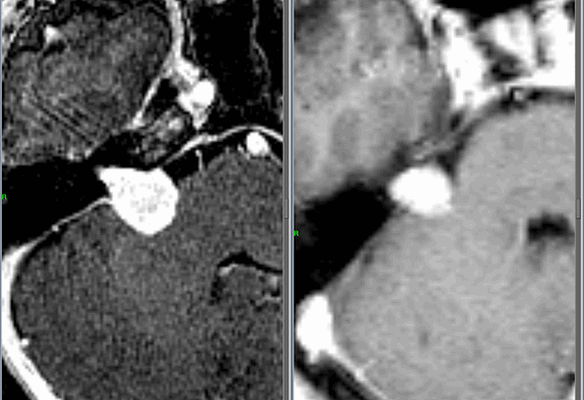

Слева - МРТпациентки М., 65 лет. Обратилась в радиохирургический центр МИБС с диагнозом-невринома правого VIII нерва. Проведено радиохирургическое лечение, доза по краю невриномы составила 13 Грей, в изоцентре опухоли 21,7 Грей.

Справа - контрольное МРТ через 1,5 года после операции. Отмечается уменьшение объёма опухоли на 47%.